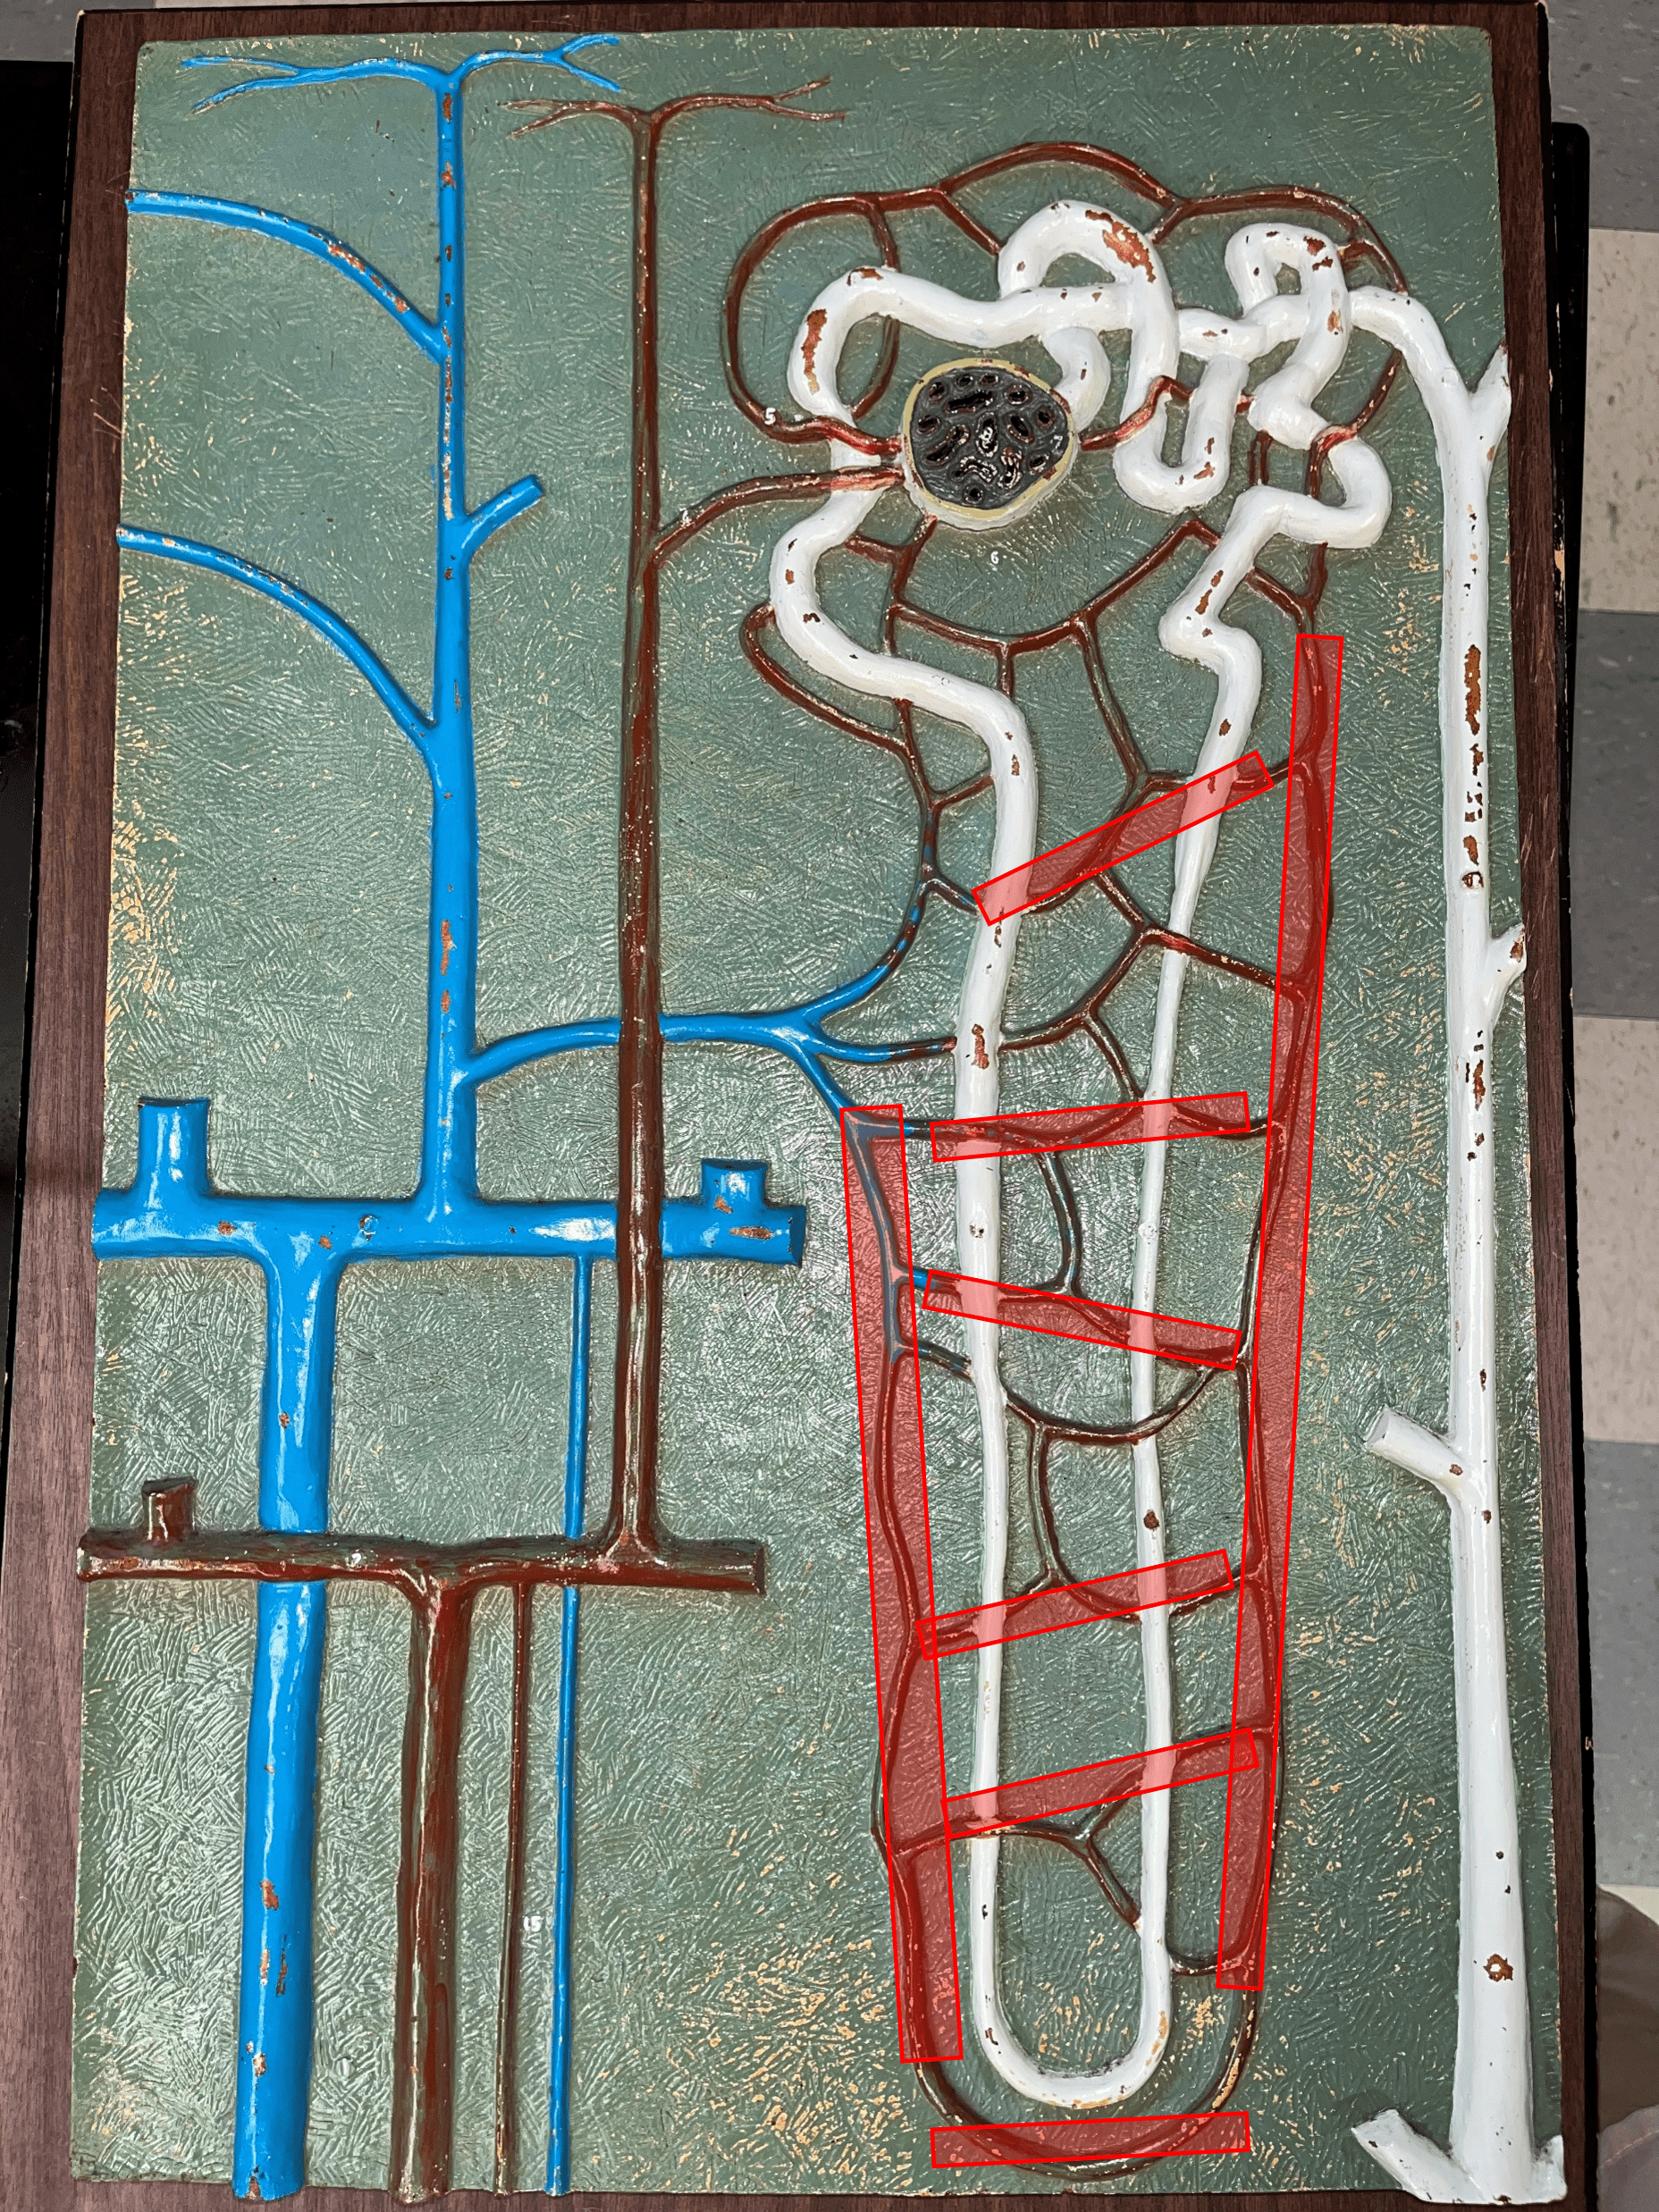

segmental artery

• Branches of the renal a.

• Branches into smaller interlobar aa.

• Branches into smaller interlobar aa.

interlobar artery

• Extends between the renal pyramids.

• Branches of a segmental a.

• Branches into smaller arcuate aa.

• Branches of a segmental a.

• Branches into smaller arcuate aa.

arcuate artery

• Extends along the base of the renal pyramids.

• Branches of an interlobar a.

• Branches into smaller interlobular aa.

• Branches of an interlobar a.

• Branches into smaller interlobular aa.

interlobular artery

• Extends through the renal cortex.

• Branches of an arcuate a.

• Branches into an afferent arteriole of a glomerulus.

• Branches of an arcuate a.

• Branches into an afferent arteriole of a glomerulus.